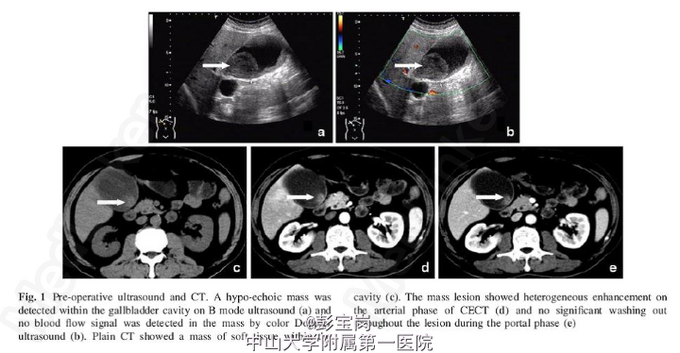

男性,66岁,因“反复右上腹痛1月余”入院。患者于1月余前无明显诱因出现右上腹痛,呈间歇性胀痛,偶伴有右侧腰背痛,可自行缓解,无伴发热、畏寒,无恶心、呕吐等不适,于当地医院就诊,查腹部CT及B超提示“胆囊等回声光团,未除外胆囊Ca并胆固醇沉积,建议行进一步检查”,予消炎、利胆等对症治疗后症状可缓解。为进一步治疗到我院就诊,门诊查腹部B超及超声造影提示“脂肪肝,肝囊肿,胆囊肿大,胆泥形成”。为求进一步手术治疗,门诊拟诊“胆囊炎并胆囊结石”收入我科。

查体无特殊;HBsAg(-)、HBcAb(+)、anti-HCV(-);肿瘤标记物:甲胎蛋白(AFP) 508 ug/L(0-20);CA19-9 458 U/L (0-40),癌胚抗原(CEA)和CA125正常范围内

术前诊断:胆囊结石、慢性胆囊炎 处理:腹腔镜胆囊切除术:术中探查胆囊张力大,炎症水肿较明显,壁稍厚,大小约8cm×6cm×2cm,与大网膜粘连。结合术前检查,术中诊断为:胆泥并慢性胆囊炎。术后切开胆囊见豆腐渣样内容物。